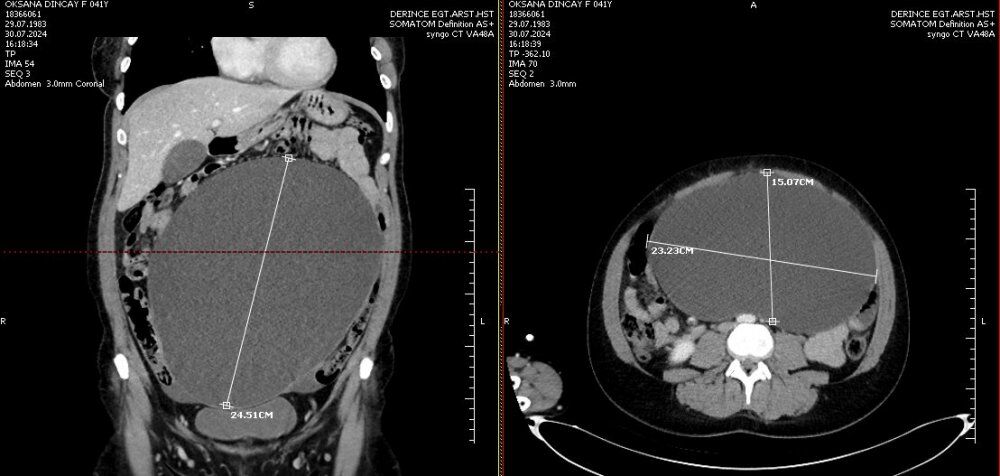

Yapılan tetkik ve değerlendirmeler sonucunda kadın hastanın karnında yumurtalığından köken aldığı düşünülen 26 cm boyutunda bir kitle saptandı.

Kapalı (Laparoskopik) yöntemle gerçekleştirilen başarılı operasyon ile hastanın karnından tam 26 cm büyüklüğünde ve 4 kilo ağırlığındaki kitle çıkarıldı. Kitle boyutu ile doktorları bile şaşırttı.